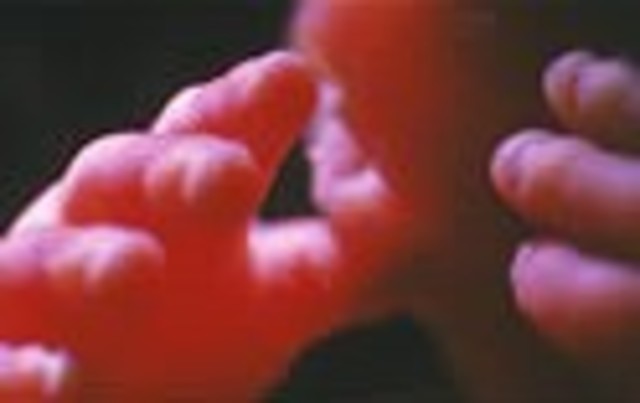

• Week 9: Fingers and Toes form

Week 9: Fingers and Toes form

The fingers and toes are vetu define. The bones atart to form.

• Week Ten: Embryo is now a Fetus

Week Ten: Embryo is now a Fetus

The developing organism is called a fetus.It is the size of a small strawberry.